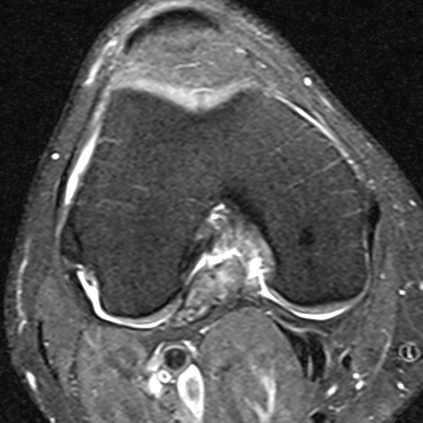

Localized / nodular

Localized PVNS of the notch

Localized posterolateral PVNS